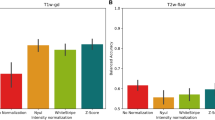

The growing interest in machine learning (ML) in healthcare is driven by the promise of improved patient care. However, how many ML algorithms are currently being used in clinical practice? While the technology is present, as demonstrated in a variety of commercial products, clinical integration is hampered by a lack of infrastructure, processes, and tools. In particular, automating the selection of relevant series for a particular algorithm remains challenging. In this work, we propose a methodology to automate the identification of brain MRI sequences so that we can automatically route the relevant inputs for further image-related algorithms. The method relies on metadata required by the Digital Imaging and Communications in Medicine (DICOM) standard, resulting in generalizability and high efficiency (less than 0.4 ms/series). To support our claims, we test our approach on two large brain MRI datasets (40,000 studies in total) from two different institutions on two different continents. We demonstrate high levels of accuracy (ranging from 97.4 to 99.96%) and generalizability across the institutions. Given the complexity and variability of brain MRI protocols, we are confident that similar techniques could be applied to other forms of radiological imaging.

Pizarro R, Assemlal HE, de Nigris D, Elliott C, Antel S, Arnold D, Shmuel A: Using deep learning algorithms to automatically identify the brain MRI contrast: implications for managing large databases. Neuroinformatics 17(1):115–130, 2019